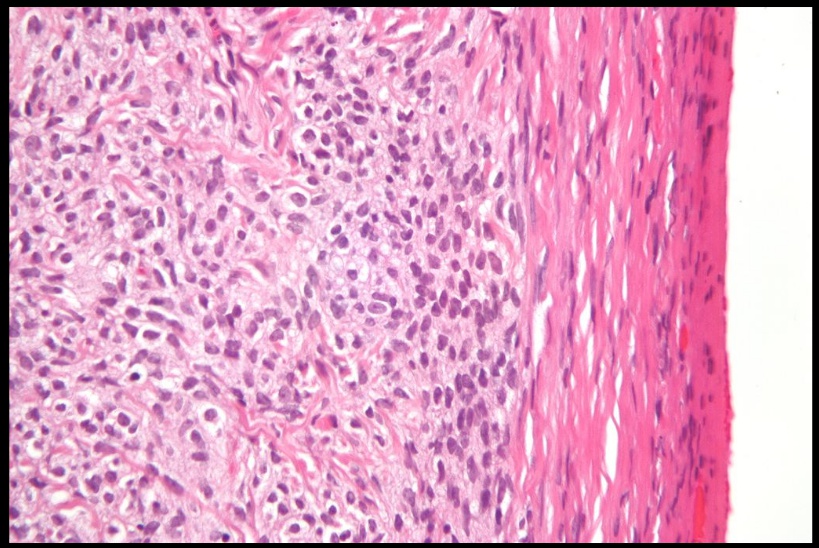

Dysgerminoma

_ Tumor composed of large cells with clear cytoplasm and central nuclei (resemble oocytes)., Dys: bad. Germ: germ cell.

Dysgerminoma. The neoplastic germ cells have clear, glycogen-filled cytoplasm and central nuclei. Fibrous septa containing lymphocytes traverse the tumor.

_Most common malignant germ cell tumor in females.,